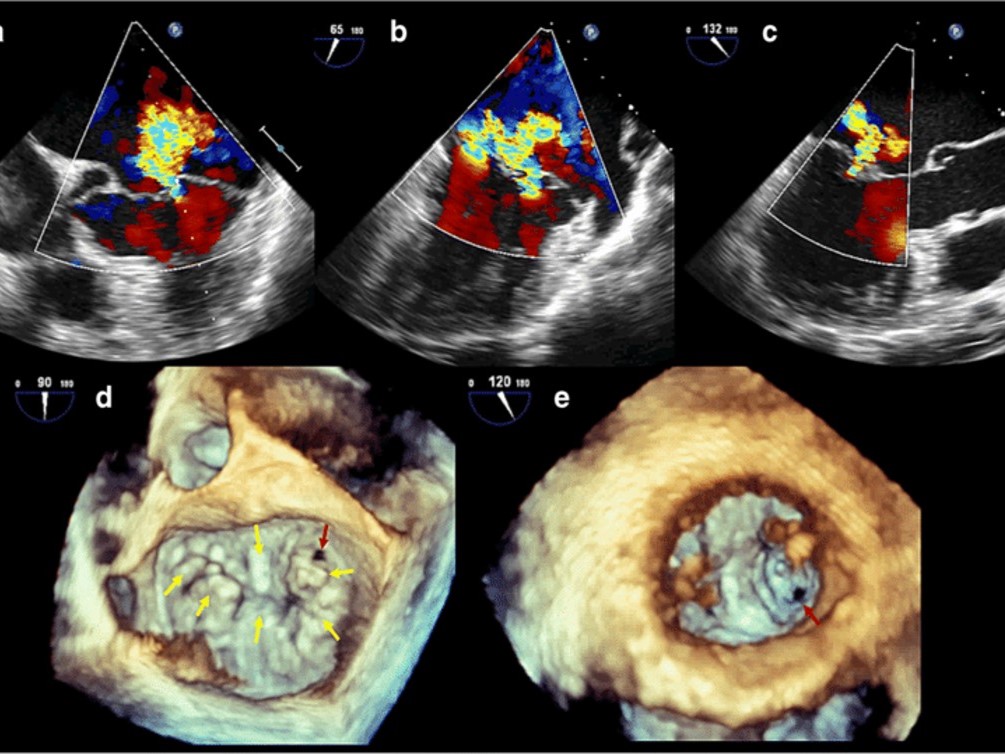

Diagnosticul se stabileste cu mare precizie prin ecocardiografie transtoracica si transesofagiana. Aceasta ne ajuta nu numai sa identificam tipul si mecanismul insuficentei mitrale, dar ne poate asista in gasirea celei mai bune si corecte metode de tratament chirurgical.

Exact opusul insuficienței mitrale, stenoza valvei mitrale este prezentată prin deficitul de deschidere a valvei fie prin blocarea mișcărilor acesteia fie prin micsorarea orificiului valvei. În această situație sângele rămâne partial blocat in atriul stang si în plămâni, cu apariția dispneei, toleranței scăzute la efort, hipertensiune pulmonara, dificultatea la respirație accentuandu-se în pozitia culcat. Responsabile pentru apariția stenozei mitrale sunt reumatismul și modificări degenerative cu calcificări importante de inel si de cuspe ale valvei mitrale. De cele mai multe ori, afectarea valvei mitrale este dubla, coexistand stenoza si insuficienta, datorita modificarilor structurale importante ale acesteia, afectiunea numindu-se boala mitrala.